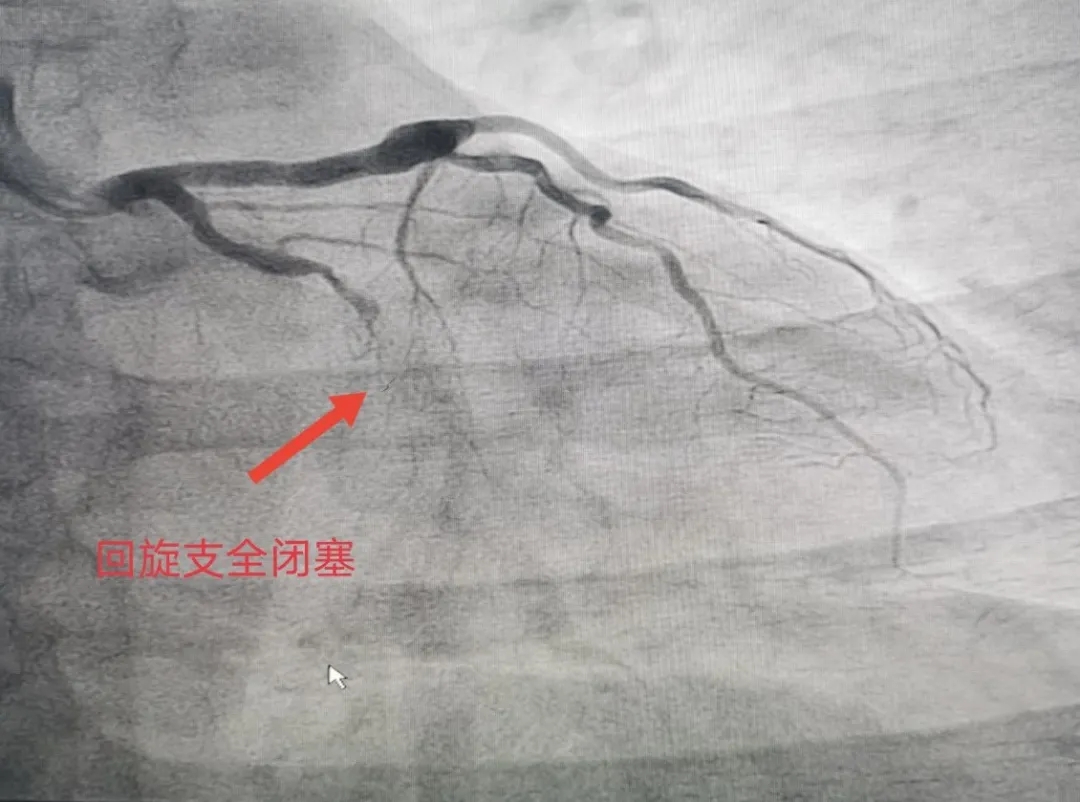

7月19日,前来医院体检的马某在检查冠状动脉造影时,显示左冠右冠分别有不同程度狭窄,冠狭窄50%左右,左回旋支全闭塞。院方立马与家属谈话同意治疗,给予NS导丝很难通过血管,又给予Fielder XT通过,判断出血管钙化严重,放支架不是最好的效果,便实施了PTCA球囊扩张治疗。经过介入团队2个半小时的努力,最终使患者受益,手术当下达到了最好的效果。患者亲属多有心脏搭桥手术,自身支架植入手术后无特殊症状,只是偶尔牙痛放射至心前区不适,本次手术后感觉轻松了很多。

当日,因急性心梗行右冠脉支架植入术的刘某,前来医院复查冠状动脉造影,影像显示左回旋支中远段全闭塞。由于患者桡动脉血管畸形,导丝难以通过,最终用了4种型号的导丝才通过,又植入1枚支架+药物洗脱球囊治疗恢复了血流。术后,患者胸憋的症状当即得到缓解,满怀感激地说 “咱们县医院介入团队技术真够过硬的,希望越来越好,为全县心血管患者谋福祉。”